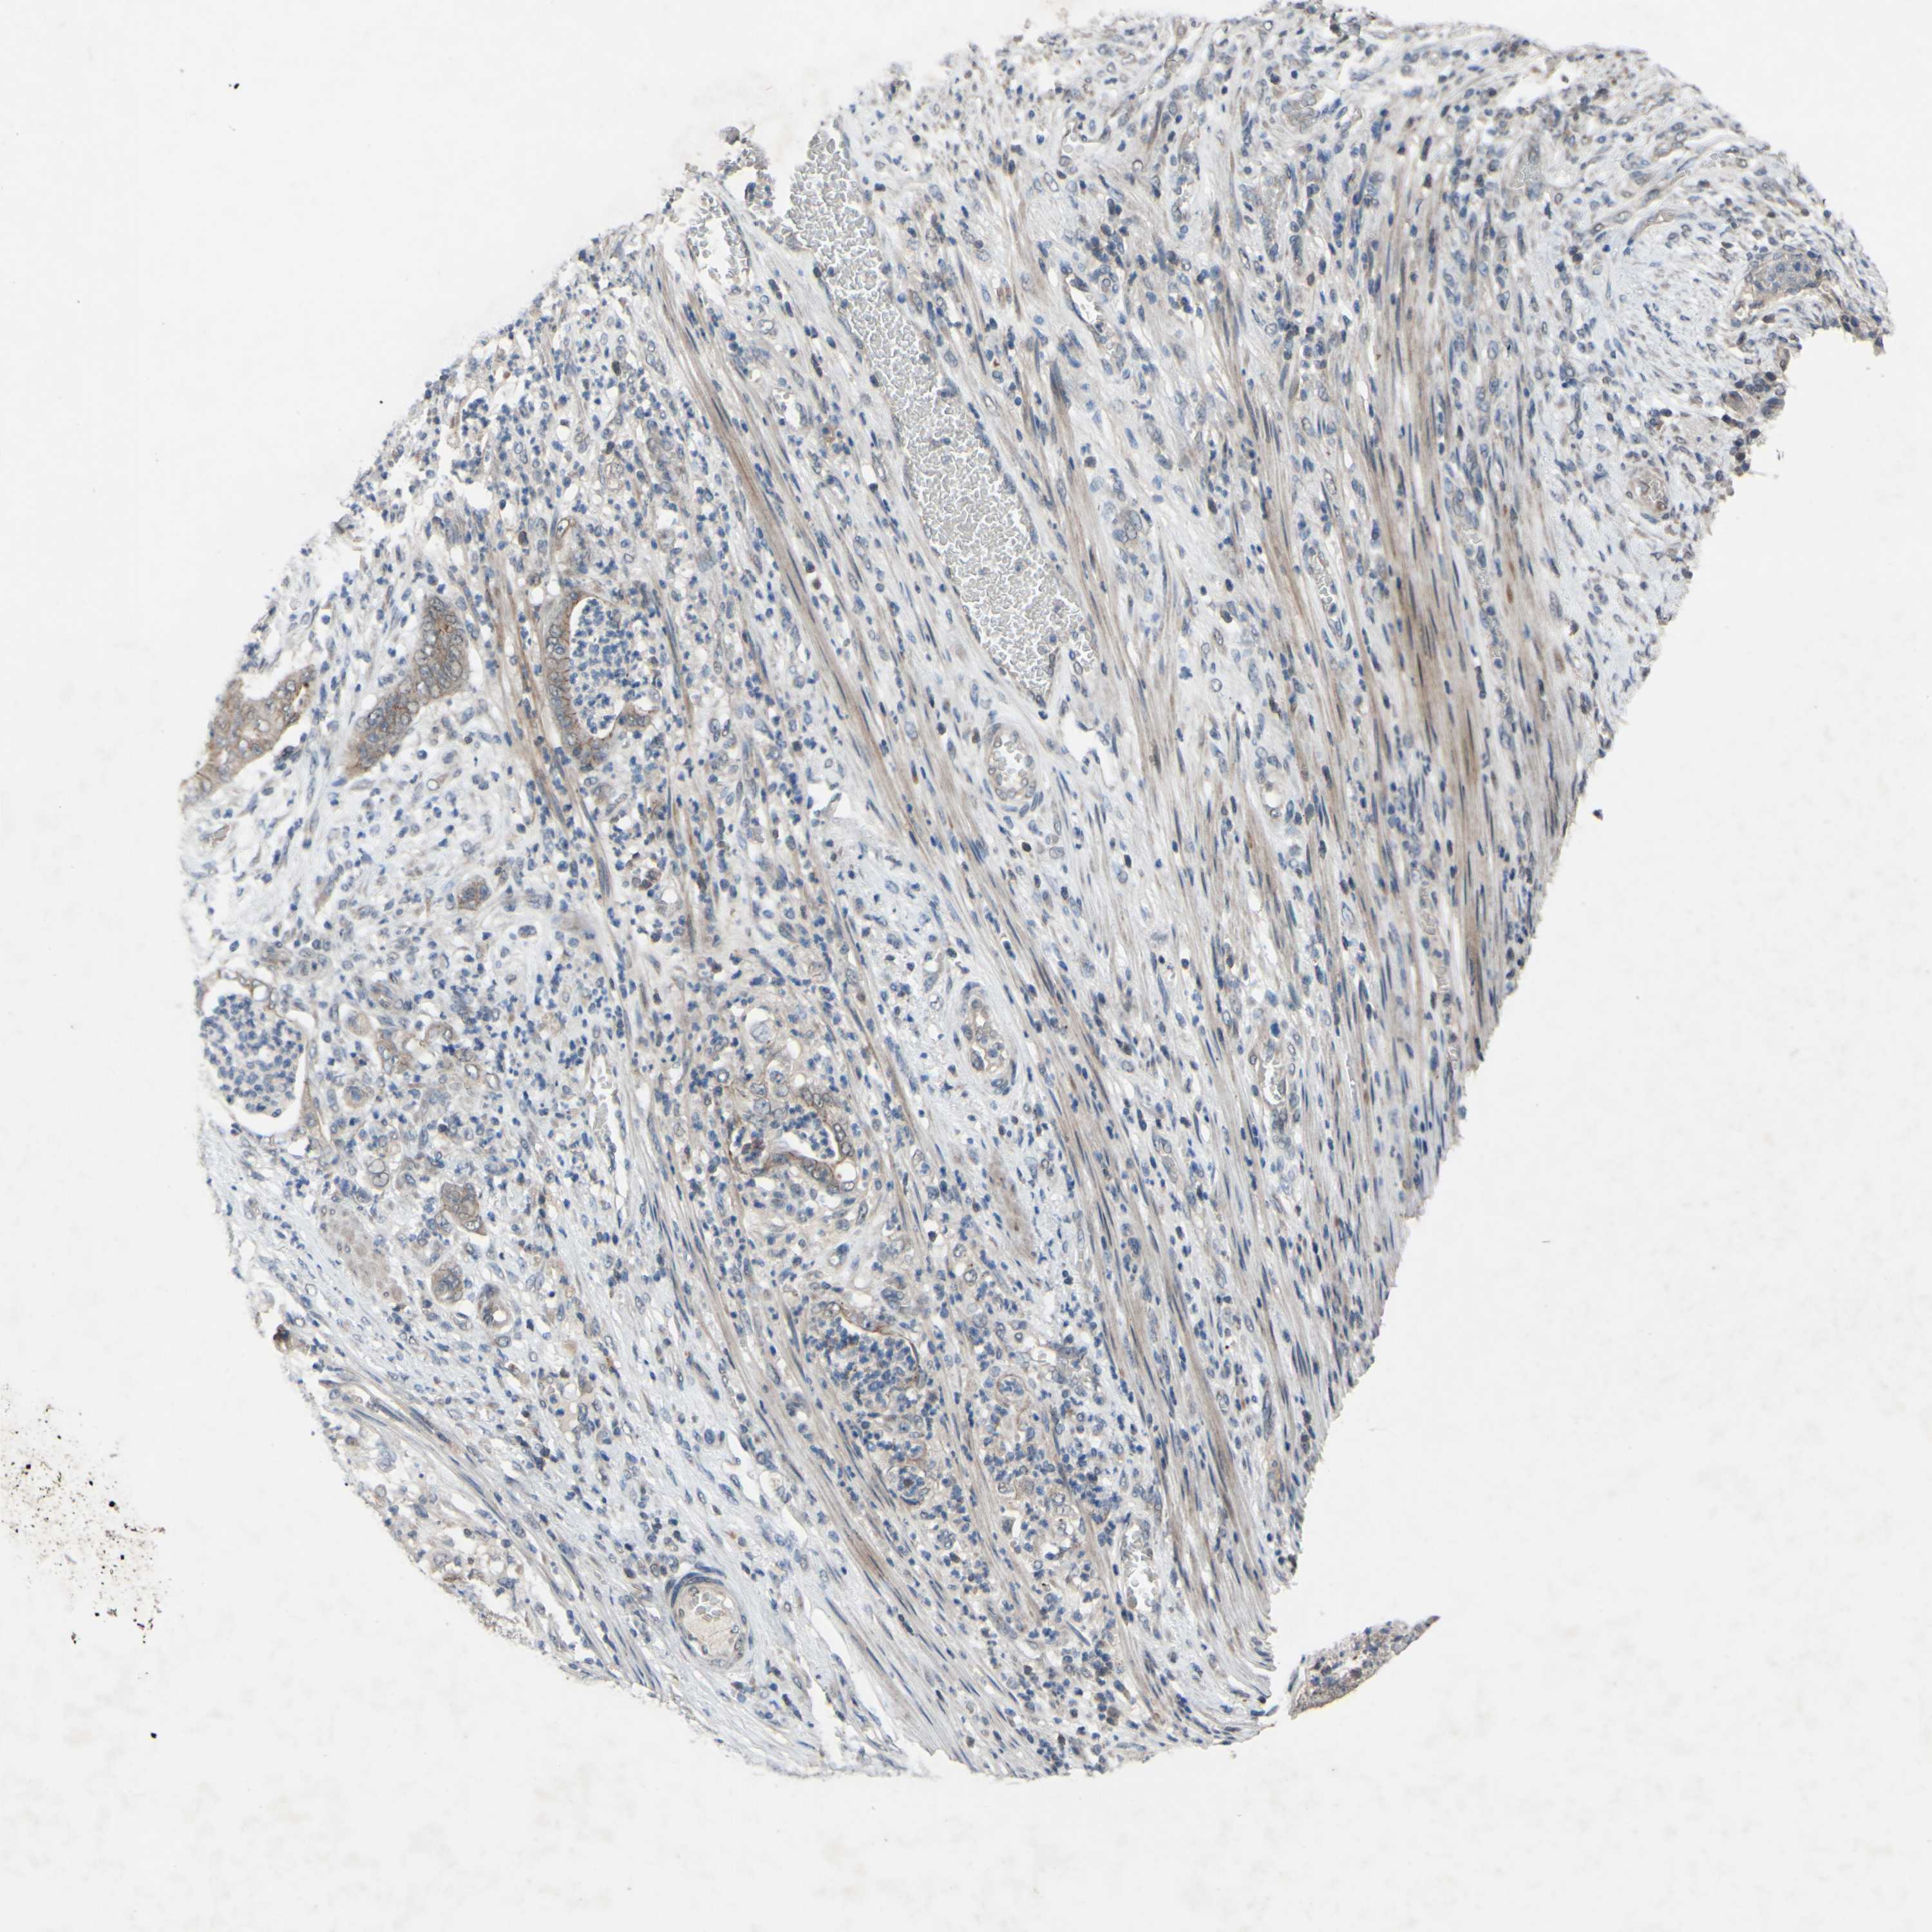

STOMACH CANCER - Protein expressioni

A mouse-over function shows sample information and annotation data. Click on an image to view it in a full screen mode. Samples can be filtered based on level of antibody staining by selecting one or several of the following categories: high, medium, low and not detected. The assay and annotation is described here.

Note that samples used for immunohistochemistry by the Human Protein Atlas do not correspond to samples in the TCGA dataset.

Antibody stainingi

Antibody staining in the annotated cell types in the current human tissue is reported as not detected, low, medium, or high, based on conventional immunohistochemistry profiling in selected tissues. This score is based on the combination of the staining intensity and fraction of stained cells.

Each image is clickable and will lead to virtual microscopy that enables deeper exploration of all samples and also displays staining intensity scores, fraction scores and subcellular localization as well as patient and tissue information for each sample.

Antibody HPA010978

Antibody HPA010979

Antibody CAB025637

Staining

High

Medium

Low

Not detected

Intensity

Strong

Moderate

Weak

Negative

Quantity

>75%

75%-25%

<25%

None

Location

Nuclear

Cytoplasmic/membranous

Cytoplasmic/membranous,nuclear

Adenocarcinoma, NOS

Adenocarcinoma, High grade